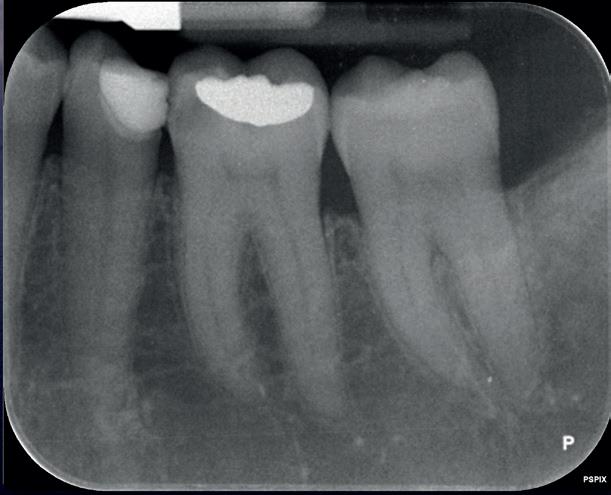

Een 47-jarige collega presenteert zich in onze verwijspraktijk voor endodontie. Hij heeft enige tijd geleden zijn kroon op de 11 laten vervangen (afbeelding 1). Omdat er geen klinische en röntgenologische aanwijzingen waren voor een periapicale laesie of een insufficiënte wortelkanaalbehandeling van de 11, werd besloten de endo, die dateerde van meer dan 30 jaar geleden, niet te reviseren (afbeelding 2). Tijdens een routinematige gebitsreiniging constateert zijn mondhygiënist een pocket van 7 mm aan de mesiopalatinale zijde van 11 (afbeelding 3). De nieuwe kroon wordt tijdelijk gecementeerd, en omdat

1: Klinische foto van bovenfront

2: Röntgenfoto van 11 met zilverstift sectie

3: Pocket palatinaal 11

4: Horizontale doorsnede CBCT met radiolucentie mesiopalatinaal van de 11

de patiënt zich zorgen maakt over deze toevalsbevinding, wil hij de 11 laten beoordelen door een endodontoloog.

Er wordt een CBCT gemaakt die een laesie aan de mesiopalatinale zijde van 11 laat zien (afbeelding 4).